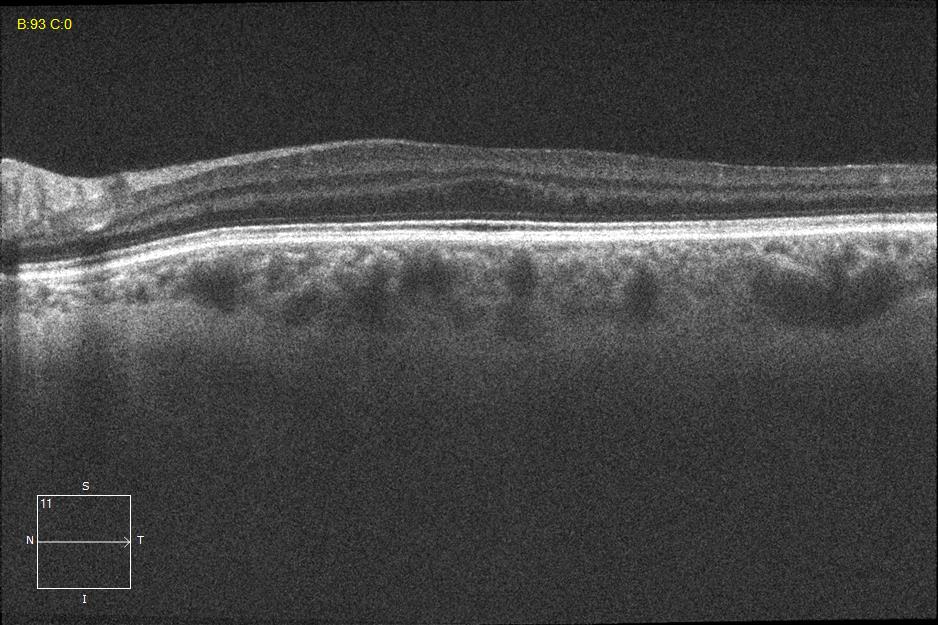

Two different patients with isolated foveal hypoplasia grade 2. The definitions of fovea plana and foveal hypoplasia have led to controversy among experts. The term fovea plane refers to the anatomical absence of a foveal pit. An estimated 3% of children with clinically normal eyes have an underdeveloped foveal pit on OCT. According to some experts, a foveal pit is not absolutely necessary for foveal cone specialization. A diagnosis of fovea plana alone does not automatically herald functional disability. It is possible to maintain adequate visual acuity in an eye with a fovea plana. Foveal hypoplasia refers to an underdeveloped fovea with vision loss. Foveal hypoplasia has also been seen in conditions such as aniridia, albinism, achromatopsia, nanophthalmus, and incontinence. pigment and premature retinopathy.

In contrast to other definitions, Thomas et al. defined foveal hypoplasia as the persistence of inner retinal layers in the fovea and developed a grading system based on optical coherence tomography features. According to this grading system, grades 2, 3, and 4 of foveal hypoplasia corresponded to the fovea plana.

Leicester Grading System for Foveal Hypoplasia;

Grade 1a foveal hypoplasia is associated with an almost normal pit resembling a “V” shape and outer segment (OS) elongation and outer nuclear layer (ONL) expansion relative to parafoveal OS and ONL lengths, respectively.

Grade 1b foveal hypoplasia is associated with a shallow indentation and OS prolongation and ONL widening relative to parafoveal OS and ONL lengths, respectively.

Grade 2 foveal hypoplasia has all the features of grade 1, except that there is no pit.

Grade 3 foveal hypoplasia represents all the features of grade 2 except that there is no lengthening of the OS segment.

Grade 4 foveal hypoplasia represents grade 3, except that ONL expansion is not present in the fovea (called the fovea plana).

Atypical foveal hypoplasia is characterized by distortion of the inner segment ellipsoid band, creating a shallow foveal pit and a hyporeflective zone.